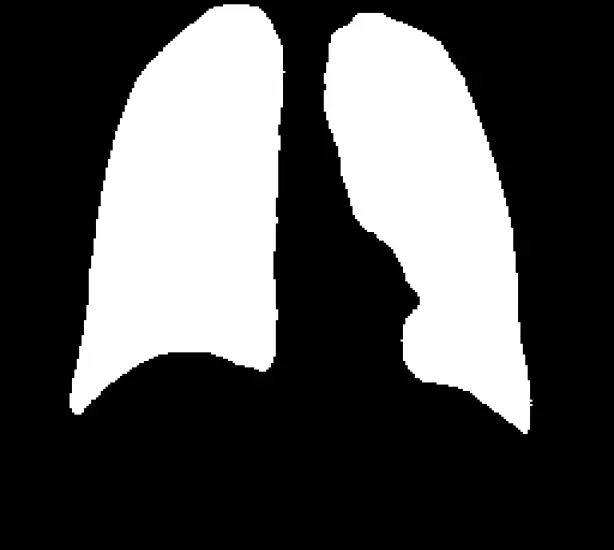

This script loads a pre-trained U-Net Keras model for lung segmentation, processes a test image, predicts the segmented lung region, and displays both the original image and the predicted mask.

It resizes the image, normalizes pixel values, applies a binary threshold to the mask, and visualizes the results using OpenCV.

The Unet Tensorflow result :